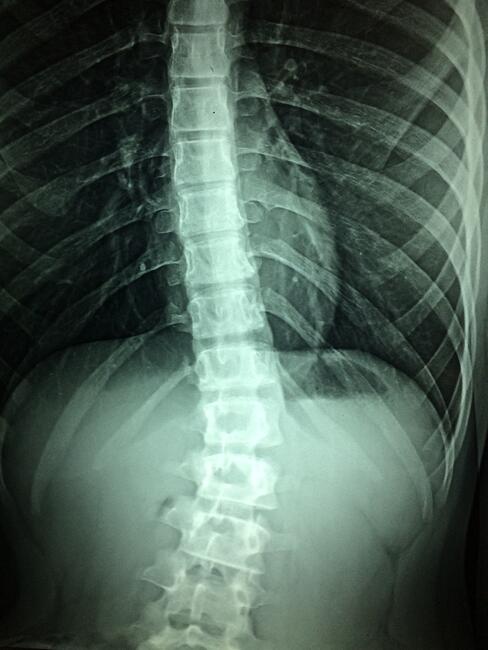

PsA Carries Risk of Vertebral Fracture

A systematic review and meta-analysis presented at the American College of Rheumatology (ACR) 2021 Convergence reveals that patients with psoriatic arthritis (PsA) have a similar risk of vertebral fracture as others with inflammatory rheumatic diseases.

“A total of 26,090 articles were identified. After two rounds of independent review by three investigators, five cohort studies met the eligibility criteria and were included into the meta-analysis,” the authors explained. “PsA is significantly associated with VF with the pooled odds ratio of 2.09 (95% CI, 1.11 – 3.96; I2 70%).”

They concluded that patients with PsA were found to carry “a significantly increased risk of prevalent VF."